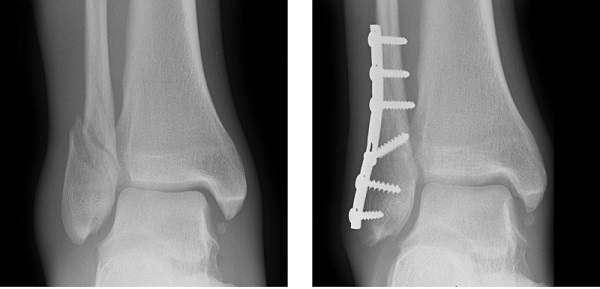

ناحيه بندي تصاوير اشعه مجهول (مثلاً جدا سازي خودکار دندان ها)